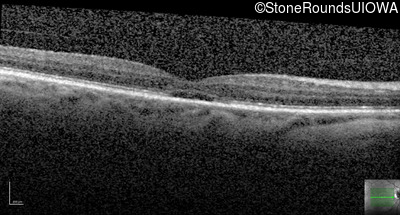

Age at visit: 56 years

The clinical features supporting the diagnosis of blue cone monochromacy in this patient include: stable reduced acuity, photophobia and very poor color vision since early childhood, a normal fundus appearance, normally sighted parents and three similarly affected male relatives on the maternal side of his family.